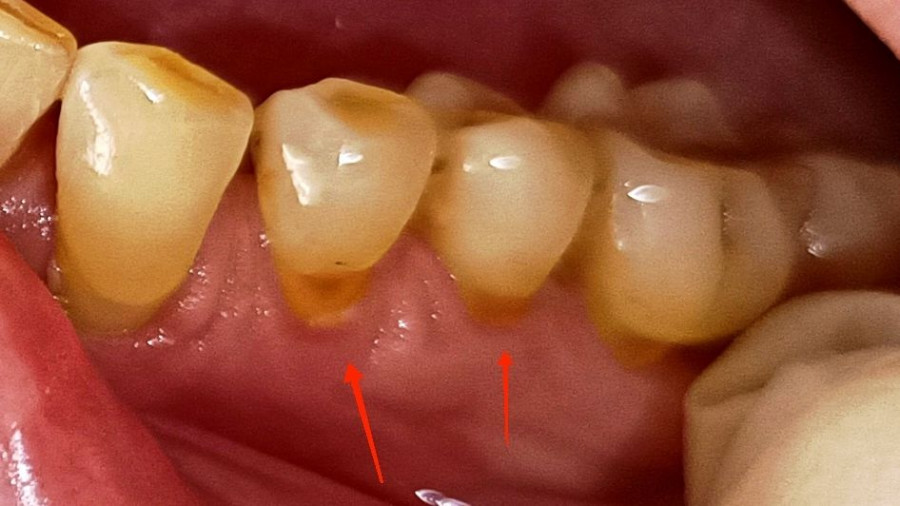

Το δυνατό τρίψιμο μπορεί να φθείρει την αδαμαντίνη των δοντιών (δηλαδή την εξωτερική, προστατευτική τους στοιβάδα) και να προκαλέσει υφίζηση των ούλων, δηλαδή να υποχωρήσουν τα ούλα και να εκτεθούν οι ρίζες των δοντιών. Αυτό οδηγεί σε ευαισθησία και αυξημένο κίνδυνο τερηδόνας.

Τερηδόνα

Αν δε ή δύναμη συνδυαστεί και με μια σκληρή οδοντόβουρτσα τότε το αποτέλεσμα είναι πολύ χειρότερο. Και εδώ έρχεται το δεύτερο λάθος που είναι η επιλογή της οδοντόβουρτσας.

Περιοδοντίτιδα